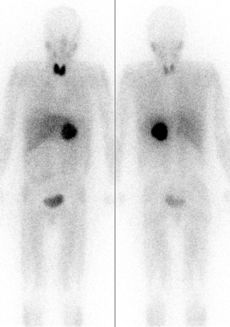

يُستخدم اعتراض امتصاص اليود الدرقي مع يوديد الپوتاسيوم في التصوير الومضاني للطب النووي والعلاج ببعض المركبات المشعة التي لا تستهدف الغدة الدرقية، مثل أيوبنگوين (MIBG)، الذي يستخدم لتصوير أو علاج أورام الأنسجة العصبية، أو الفيبرينوجين المعالج باليود، والذي يستخدم في مسح الفيبرينوجين لفحص التجلط. تحتوي هذه المركبات على اليود، ولكن ليس في شكل يوديد. ومع ذلك، نظراً لأنه قد يتم استقلابه في النهاية أو تحطيمه إلى يوديد مشع، فمن الشائع إعطاء يوديد البوتاسيوم غير المشع للتأكد من أن اليوديد من هذه الأدوية المشعة لا يتم عزله عن طريق التقارب الطبيعي للغدة الدرقية لليوديد.